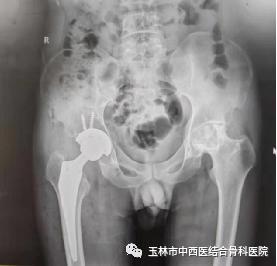

图一为患者术前DR结果

图二为患者髋关节置换术后DR结果

36岁的卢先生来到玉林市中西医结合骨科医院,入住髋关节一科,经该科黎观保主任和刘桐源医生询问病史、查体、阅片后诊断为“双侧股骨头坏死”,为卢先生制定了“直接前方入路(DAA)人工全髋关节置换术”的治疗方案。

手术当日,髋关节一科黎观保主任带领团队在麻醉科、手术室的配合下为卢先生进行了直接前路(DAA)微创人工右髋关节置换手术。由于手术创伤小,术中几乎没有出血,对肌肉组织损伤也非常轻微,麻醉苏醒后的卢先生便可立即自主活动髋关节,能够轻松抬腿了,而且自觉没有明显疼痛感。

术后第一天就可在病房内不扶拐行走,没有明显跛行步态以及任何姿势的限制,还能完成深蹲、盘腿等动作,连病房里的病友都感叹手术的成功。其实,这一切主要归功于DAA。